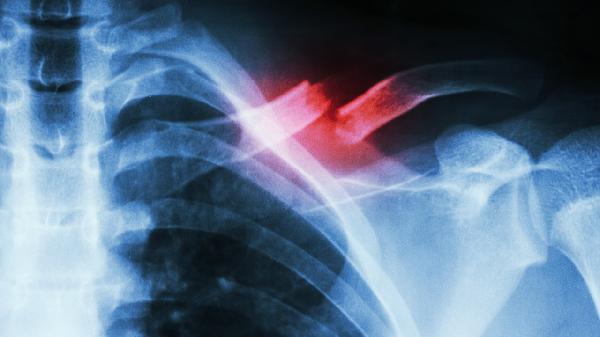

鎖骨粉碎性骨折后遺癥是啥